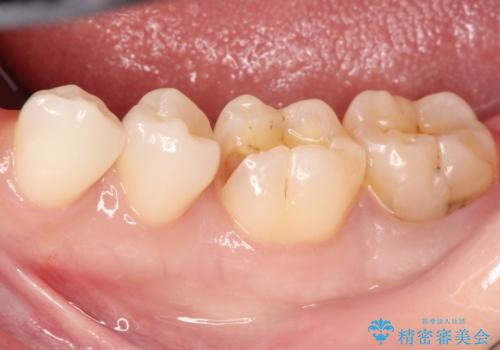

詰め物が外れた セラミックによる精密な修復

- 金属の詰め物がはずれてしまったので、精度の良いセラミックをいれたいのとのこと来院されました。

セラミックインレーにて治療することとなりました。

拡大鏡を使用して精度の高いインレーを装着しました。